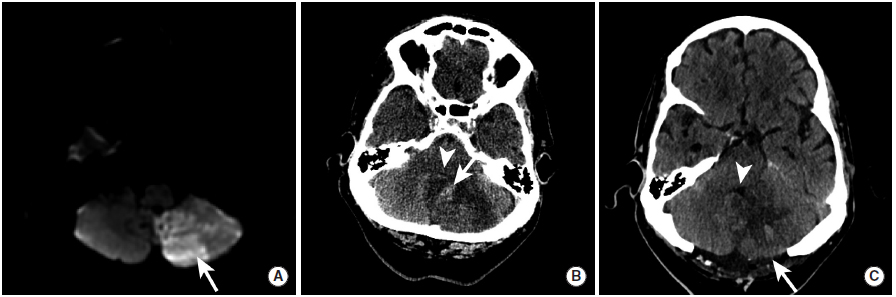

图11

本例患者左侧小脑后下动脉供血区发生脑梗死,并出现了出血性转化,此后接受了后颅窝减压手术。

图A:MRI的DWI序列显示左侧小脑后下动脉供血区弥散受限。

图B:3天后,患者脑梗死区域内出现HI-2型出血性转化(长尾箭头),脑组织肿胀,第四脑室消失(三角箭头)。

图C:患者接受去骨瓣减压术(长尾箭头)后,复查可见第四脑室(三角箭头)。